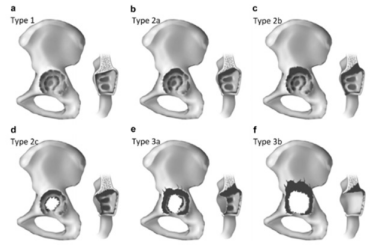

The Burch-Schneider (BS) plate (Figure 1) has been in constant use since its introduction in 1974. In 1987, however, the material was switched from steel to titanium, with the aim of improving its utility and long-term outcome. Our institution commonly uses the BS plate for pelvis reconstructions. In the preoperative planning stage, we routinely perform anteroposterior (AP) x-ray of the pelvis to determine the pelvic defects, proximalization of the center of rotation, osteolysis of the os ischii and teardrop, and the position of implants with respect to the Köhlers ilioischial line. All of these parameters can influence re-implantation of the acetabular component, particularly as they help to determine the underlying acetabular defects. We also routinely use the Paprosky classification system [1] when assessing which spherical acetabular components to use for re-implantation (Figure 2), considering every degree for its effect on the stability of the spherical component to be implanted. Most of our cases were IIIa than IIIb as defect of the acetabulum. For patients with Paprosky defect IIIa–defined as a proximolateral defect without pelvic discontinuity – the plate is better implanted into pelvis, as it will overcome the loss integrity in the posterior wall due to the defect. Considering the literature, Regis et al. [2] reported the protrusion and deficiency of the medial wall acetabulum and that the defect can effect more than 50% of resting bone. Scott et al. [3] also reported that excessive defects of the acetabulum, without healing potential, are indicators for use of bone grafts in the reconstruction procedure. On the other hand, Hur et al. [4] reported on a mechanical aspect, in that osteosystesis of the pelvis occurs due to pelvic discontinuity with press-fit acetabulum when the BS cage is used, even when the BS cage did not present any superficial results (i.e. functional outcomes).

The algorithms of a decision to implant the BS plate are mainly derived from the preoperative x-ray findings, on a patient-bypatient basis. It is important to determine whether there is a pelvic discontinuity. If we are to consider the pelvis as united, then it is important to consider perioperative findings of any acetabular deficit. Proximalization of the THR within 3 cm over the upper obturator line signifies that discontinuity is less probable. The perioperative step that proceeds this finding will then consist of a decision as to what is sufficient contact for the rest of affected bone with the implant. Finally, the Paprosky defect can be defined [11,12]. In patients with Paprosky defect IIIa, a trabecular titanium system may be used, which unfortunately is not suitable for use in individuals with low physical demand because of its cost. When we consider that stability is related to contact with the bone, then a Paprosky defect IIIb type becomes an important consideration.

The perioperative step will involve determining whether there is acute pelvic dissociation with sufficient bone for healing, or if there might be a chronic disjunction with insufficient bone to support good healing. Paprosky defect IIIa can be defined by a proximolateral migration of more than 3 cm over the obturator line, osteolysis of the os oschii (to 15 mm under the obturator line), destruction (even partially) of the teardrop, position of the component laterally from the Köhlers line, intact ilioischial and iliopubic lines, and lack of pelvic disjunction. Paprosky defect IIIb, on the other hand, can be defined by less than 40% contact between the bone and implant. Circumference bone defect involves more than half the circular portion of the acetabulum (between 9-5 hours), lysis of the os ischii of more than 15 mm under the upper obturator line, complete destruction of the teardrop, medial migration from the Köhlers line, and proximomedial migration of more than 3 cm from the obturator line.